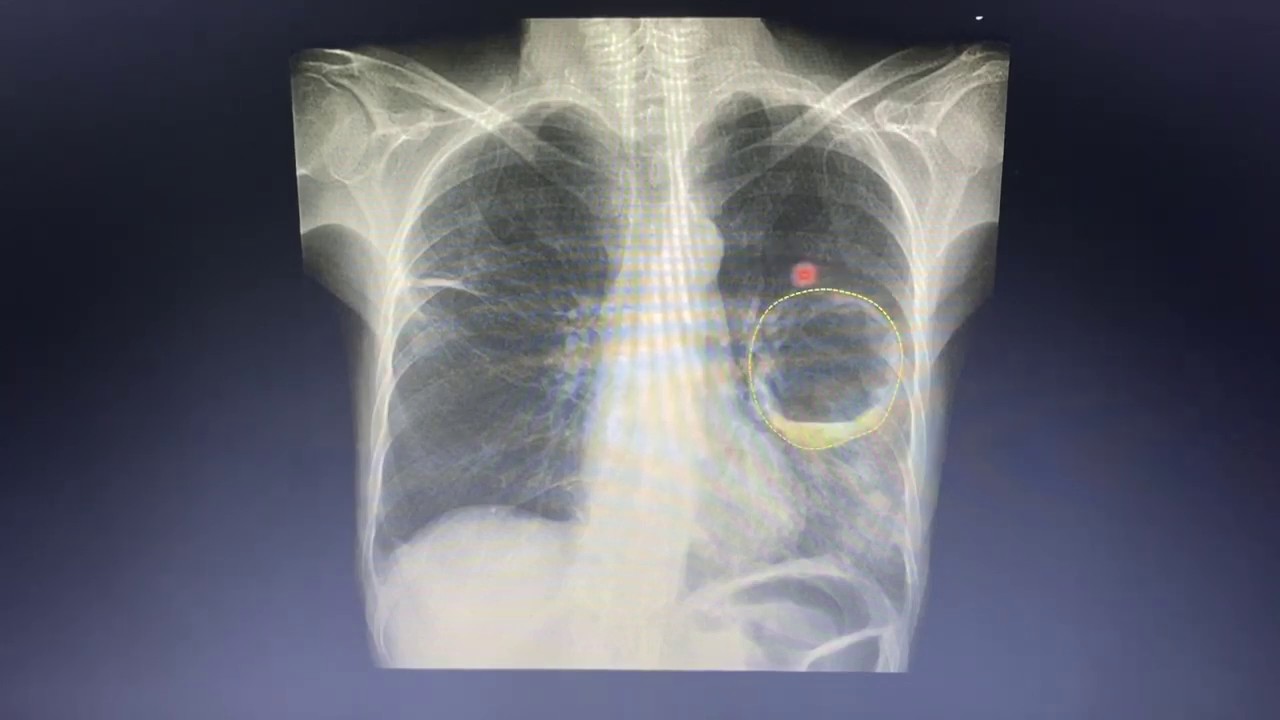

ensino primário lá né então você vai ver um paciente com escavação o seu raciocínio mais um mesmo assim meio é um paciente com ele e fala comigo Lia está assistindo não vai ser diferente né só quero explorar que às vezes a gente tem que pensar contra tuberculose é progressiva Onde tiver alterações que podem indicar progressão disseminação hematogênica acontecendo a familiar a gente vê aqui a direita né a tomografia de tórax tiveram acho que elas são bem bonitinho né com paredes bem espessadas que é o caso de voz o maior prazer Jesus as escavação né a

formação expansiva que está vendo a linha redondada ela tem paredes espessadas e no interior um palestino líquido ou não aqui tem outros dias a gente vai mais para frente aqui é uma Peça Nossa fica bonito né ele uma peça de queijo também como se é bem escavado escavação geralmente da tuberculose ela não é é regular né Ela é justamente bem regular mesmo Acontece uma necrose hialina necrose caseosa aqui na geografia e que tem que tomar um treinado Mas vocês vão pegar esse conteúdo quem tem pouca experiência você vai ver né amor Qual cidade é arredondado

aqui né no terço superior do pulmão direito ventilado superior né E aí tem um pouquinho de gás no interior dela tipo assim dúvida aí então a escavação Ela acabou de falar aqui naquele serviu para mostrar mais os casos aqui xaxá do chão pequeno tão irregular Cravinhos depois eu vou mostrar um Mônico que é se matador você não esqueça inclusive diagnósticos diferenciais de escalação de caridade a disseminação humilhar transformador gente olha só a peça é tudo que a gente vê lá na tomografia essa neste isso né parece milho Mia milhar é são os meninos ver quem

né bacteriana outra é só subir cozzi pode ser tubercular então consolidação já fica com essa você pode subir culotes aqui uma chave uma criança a consolidação lobar né a gente é não sabemos também que pelo menos na imagem né grupo grande aéreo de permeio Mas aquela dica que eu dei a cintura aqui tá mais retificada não tá tão transformada para cima